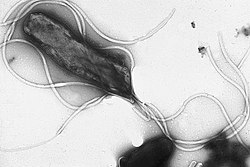

Bakterija elektronskim mikroskopom.

Helicobacter pylori je gram-negativna bakterija koja naseljava različite dijelove želuca i dvanaesnika, gdje uzrokuje upalu slabog intenziteta koja je čvrsto povezana sa nastankom ulkusne bolesti (peptički ulkus).